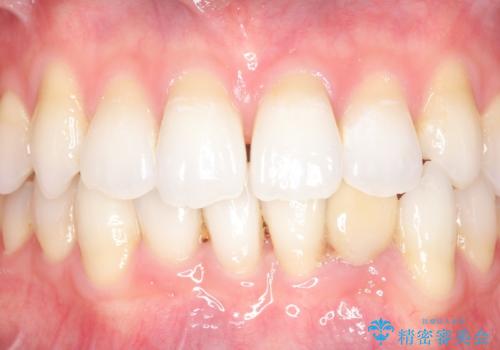

今回用いたオールセラミッククラウンはジルコニアフレームという白い素材の上にセラミックを盛っているため、審美性が非常に高いのが特徴です。

また、ジルコニアは人工ダイヤモンドの材料にも使われているほど高い強度を持っており、そのためオールセラミッククラウンは審美性だけでなく、奥歯やブリッジの補綴も可能とするクラウンです。